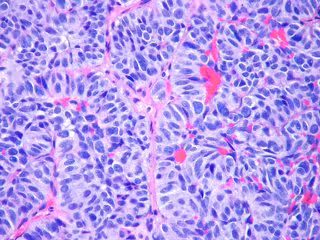

Metástasis pulmón

Foto: FLICKR/PULMONARY PATHOLOGY/ CC BY-SA 2.0